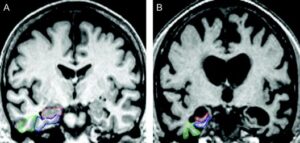

Scientists observed that women transitioning through menopause showed measurable changes in brain structure, metabolism, and energy use. These changes closely resemble patterns commonly associated with early Alzheimer’s disease — even in women who showed no outward signs of cognitive decline.

Subtle structural brain changes

Early markers linked to memory and learning regions